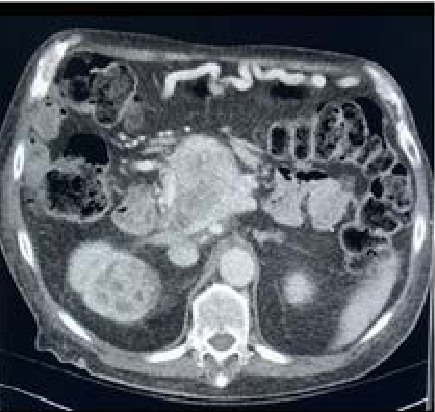

Renal Cell Carcinoma with Lung Metastasis in Association with Scleroderma

Attapon Cheepsattayakorn, Ruangrong Cheepsattayakorn and Porntep Siriwanarangsun. 5(12): 01-05.